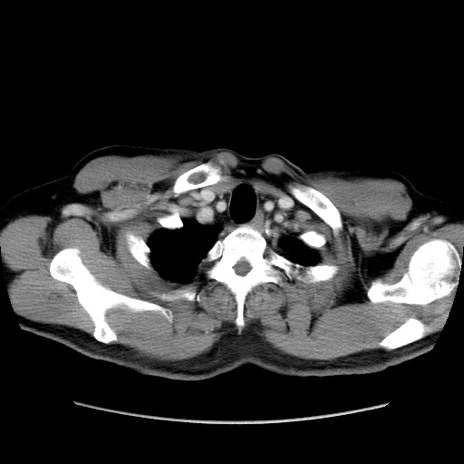

矢状断像

【症例】60歳代 男性

【主訴】右鼠径部膨隆

【現病歴】1年程前より右鼠径部膨隆あり。自己にて還納可能だったため放置していた。3時間前より右鼠径部の脱出を認め、還納困難となり受診。

【既往歴】高血圧

【身体所見】右鼠径部に小児頭大の膨隆あり。弾性硬であり、用手還納は困難。左鼠径部にも膨隆を認める。脱出はなし。

【データ】WBC 15500、CRP 測定なし